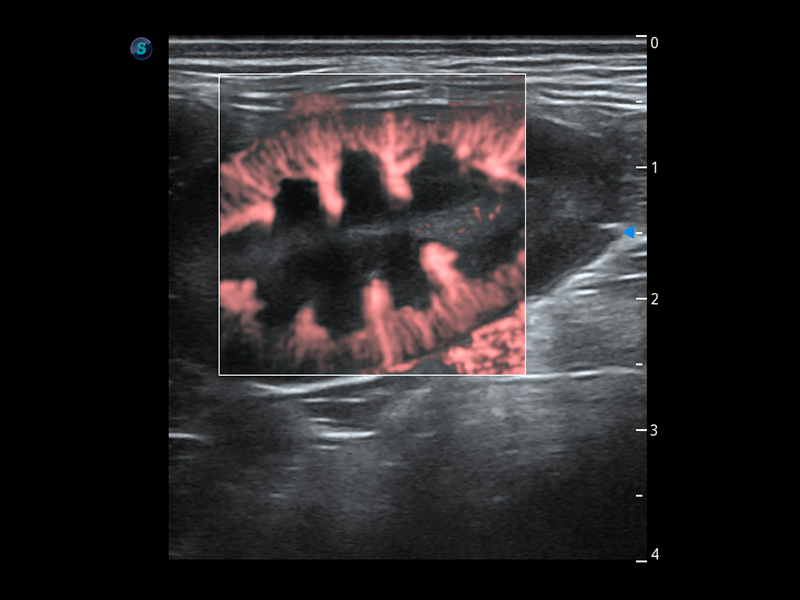

优异的基础图像

(犬)肾脏血流

PDI 能量多普勒血流

提供高灵敏度和空间分辦率的血流图像,获得更加真实和丰富的诊断信息。

SR Flow 高分辨率血流成像

能够清晰显示细小、低速血流图像,获取传统彩色多普勒技术难以得到的细节和信息。